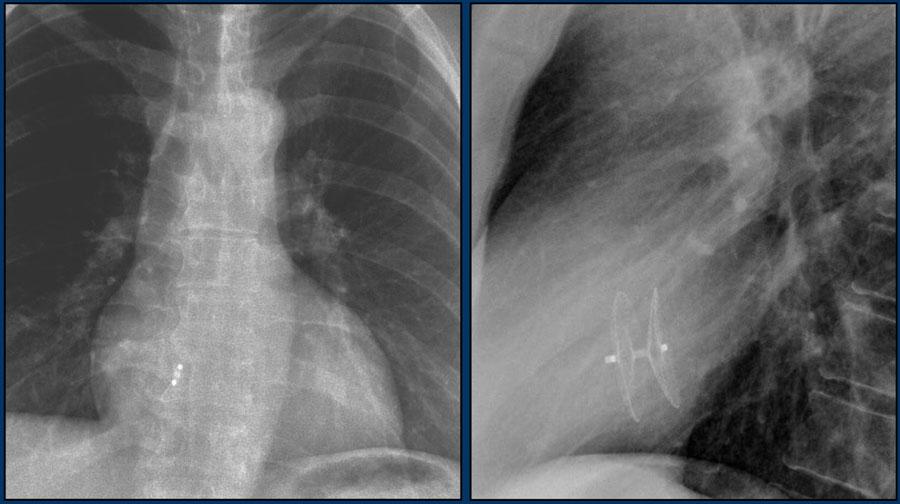

Các hình ảnh cho thấy máy tạo nhịp tim với điện cực nhĩ và điện cực thất.

Đầu điện cực nhĩ hướng lên trên và ra trước, vì vị trí lý tưởng là trong tiểu nhĩ phải, nơi điện cực được neo chặt vào các bè cơ thô.

Đầu điện cực thất được đặt tại mỏm thất phải, vị trí này nằm ở bên trái cột sống trên phim X-quang ngực thẳng và ở phía trước trên phim chụp nghiêng.